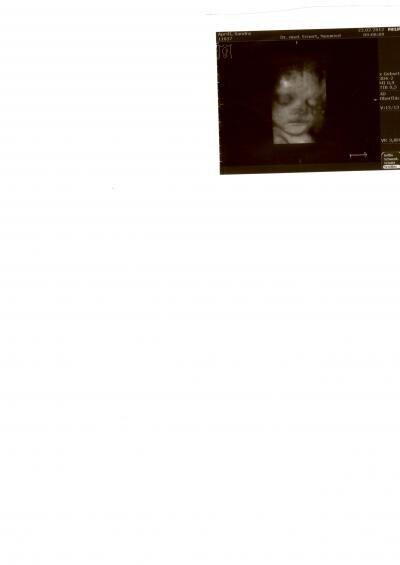

Huhu Also ich war heute beim Frauenarzt,und was soll ich sagen dem mimimann geht es gut,er ist 2600gr. schwer und 48 cm. groß und das in der 33ssw+1 Der Kaiserschnitttermin ist für den 21.3.2012 festgelegt also 37 ssw+0 Bin ja mal gespannt mit was für maßen er auf die Welt kommt!!!Bei der letzten VU vor knapp 3 Wochen hatte er 1800gr. und mein Bauch ist von 101 auf 105 gewachsen Bin ja mal gespannt und freu mich riesig aufs und Ich hänge ein Bild von heute mit dran!!!!!Bin sooooooooooooooooverliebt Lg Sanny

Bild zu Bauchzwerg - Forum für April - Mamis

Oh da hat er ganz schön zugenommen. Ist ja nicht mejhr lang dann kannst ihn im Arm Halten. Schönes Bild von de Kleinen

Wow ein fast fertiger Zwerg!! ;-) Schön das es deinem Baby so gut geht!!

Hallo Sanny, Gratuliere zu den guten Neuigkeiten! Ein total süßes US Bild! Von den Werten liegen unsere Zwerge ja ziemlich gleich: meiner hatte vor knapp 3 Wochen ca. 1760g und heute ca. 2630g. Ich finde das verdammt viel an Zunahme und mache mir Gedanken. Aber wenn dein Zwerg schon 3 Wochen vor ET geholt wird, wird es ja mit dem Gewicht nicht so extrem werden! Liebe Grüße Sonja